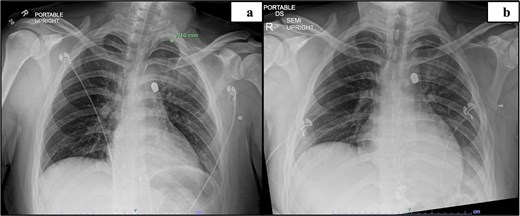

Trauma workup imaging began with a chest X-ray (CXR), triggering a chest CT given the bullet’s location in the mediastinum. With the bullet near the great vessels, a transthoracic echocardiography (TTE) and a CT using a cardiac gated/dissection protocol were obtained. The visualization of vasculature and normal anatomy was limited by metallic artifact from the foreign body (Fig. 1). The chest CT demonstrated the largest bullet fragment located in the region of the aortopulmonary window, with no measurable distance between the bullet fragment and inferomedial margin of the aortic arch (Fig. 2). Less than 2 mm of separation was visualized between the bullet and the superior aspect of the left main pulmonary artery (Fig. 2). There was no contrast extravasation from the vasculature to suggest active bleeding, and there was no obvious mediastinal fluid collection / hematoma. TTE also visualized the aortic arch and showed no clear injury with laminar flow across the aorta. His initial CXR demonstrated a normal cardio-mediastinal silhouette (Fig. 1a). A small pneumothorax was seen with 2 mm pleural separation but repeat CXR did not indicate expansion, so chest tube placement was deferred (Fig. 1a and b). Upper extremity imaging suggested soft tissue laceration and bullet trajectory without arterial damage.

Preoperative imaging indicating the location of the projectile and image obstruction by metal artifact: Initial CXR (a), day 2 CXR (b).